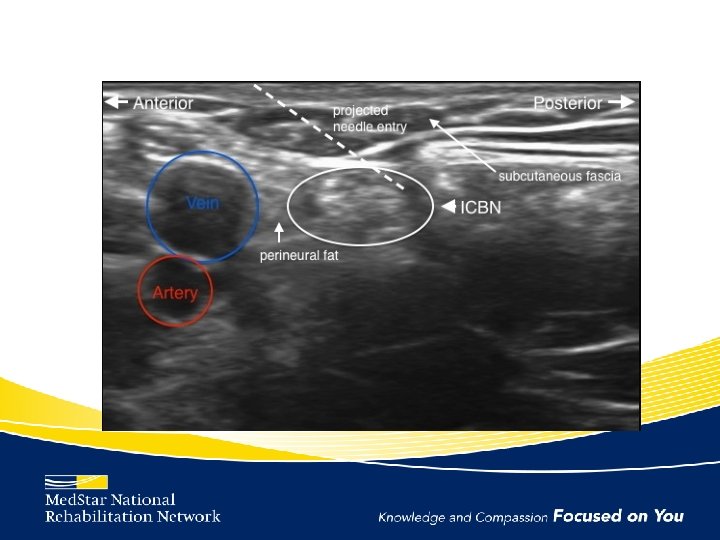

Intercostobrachial Nerve • Cutaneous branch of 2 nd intercostal nerve (T 2) • Supplies the posterior and medial upper arm, axilla, and lateral chest wall – Much anatomic variation • Increase risk of injury during ALND

Intercostobrachial Neuralgia Management • Intercostobrachial nerve block

Intercostobrachial Nerve Block Technique